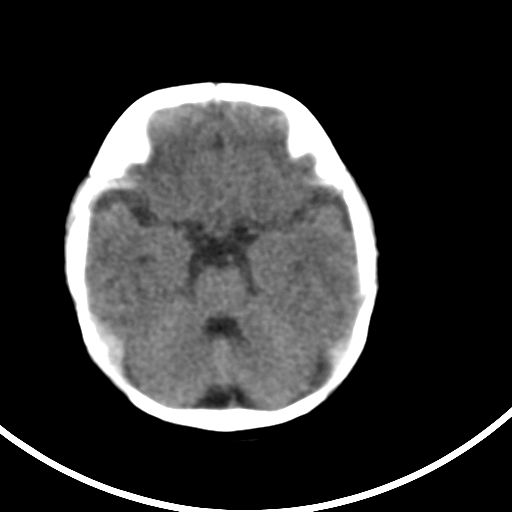

新生儿3天,超过预产期5天剖宫产,有缺氧病史,具体评分不详,现反应差,肌张力低,前囟平,原始反射存在,无苦闹等。

正常

颅底骨质影,正常颅脑表现。

正常颅脑表现。

kaolv小脑幕,后纵裂区蛛网膜下腔出血;轻度脑肿胀

未见明显异常

矢状窦旁征——支持蛛网膜下腔出血

颅脑ct平扫未见异常。

新生儿正常颅内表现

sah。